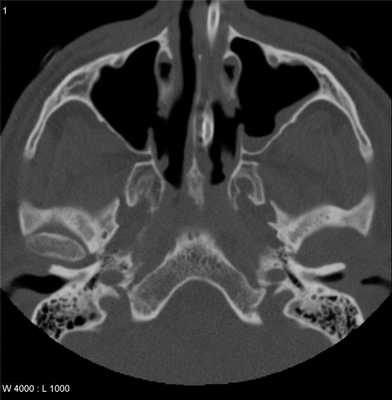

Во время КТ получают послойные снимки височной кости и окружающих тканей в трех плоскостях. Толщина среза составляет всего несколько миллиметров, что позволяет врачу-рентгенологу рассмотреть не только все анатомические образования, но и минимальные патологические изменения.

На полученных снимках хорошо видны следующие структуры:

пирамида височной кости;

ячейки и антрум сосцевидного отростка;

улитка, преддверие, передний и задний полукружный каналы;

слуховые косточки среднего уха;

стенки наружного слухового прохода;

Снимок (томограмма) височных костей в осевой проекции